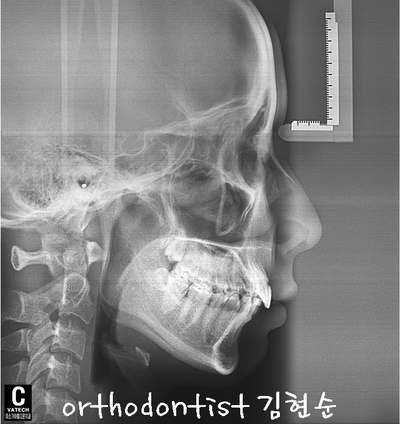

세라믹 치과 오시는 길 - 돌출 교정 - 교정 문의 환자 : 김 0 0 나이 : 24 세 F 교정 사유 : 치아 돌출 / 턱관절 호소 앞면 비대칭이 보입니다 웃을 때도 약간 삐뚤어 보입니다 입도 돌출된 모습을 확인할 수 있습니다 mi...

교정 문의 환자 : 김 0 0

나이 : 24 세 F

교정 사유 : 치아 돌출 / 턱관절 호소